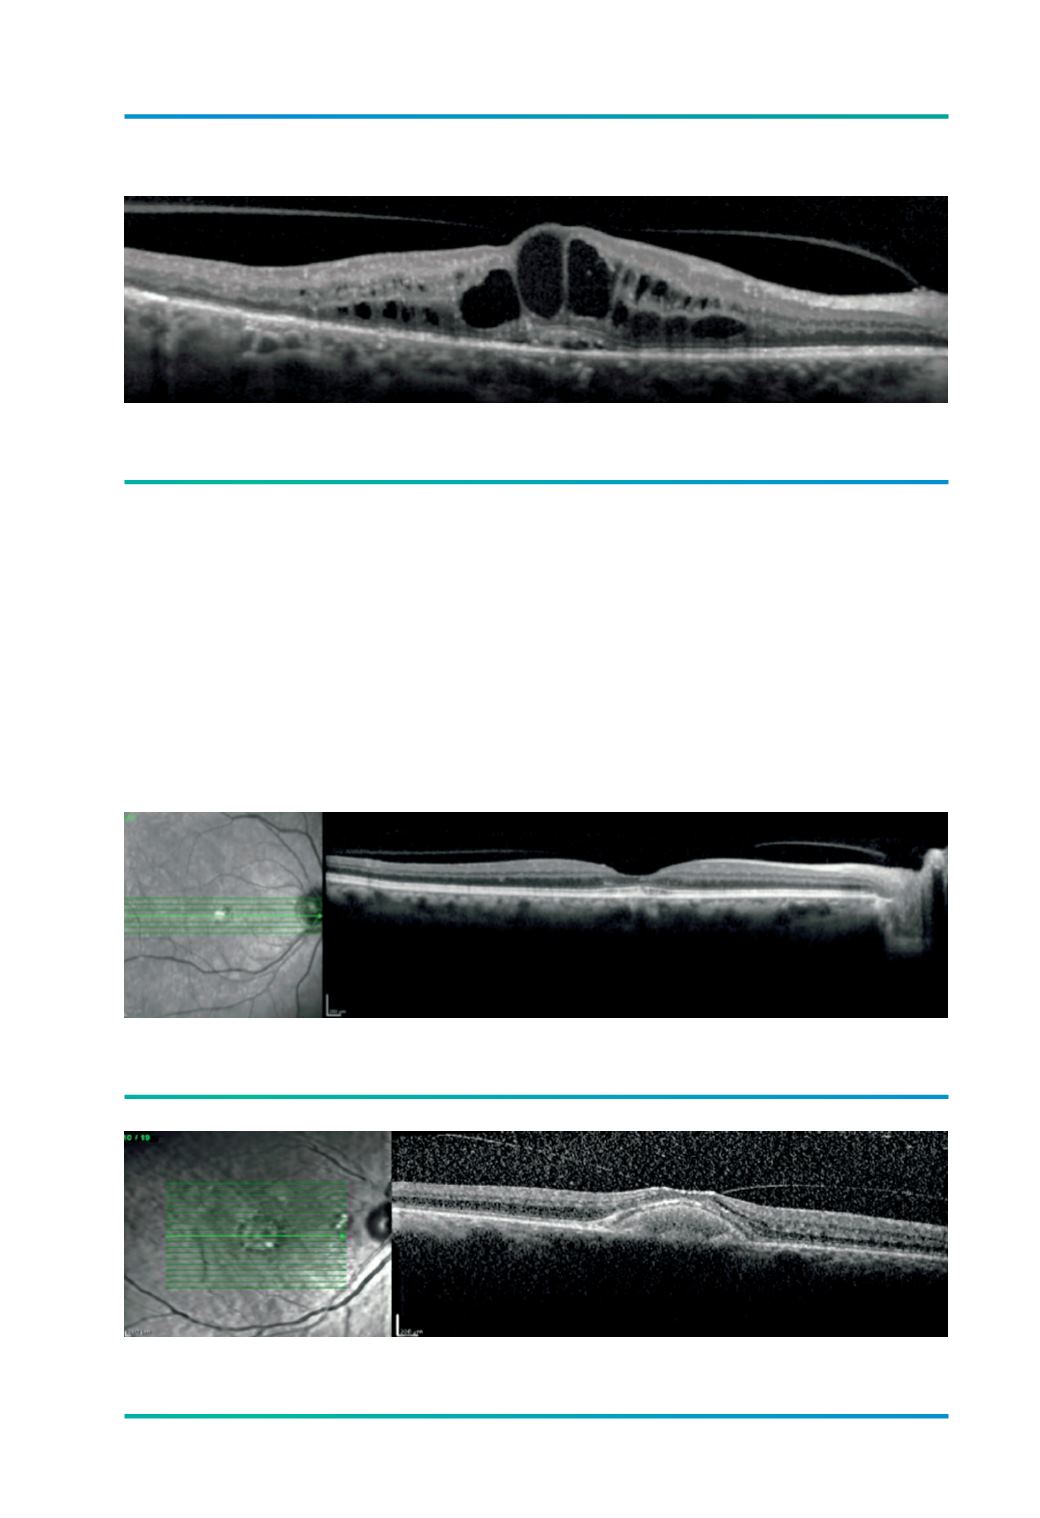

Figura 3.

TVM focal associada a EMD.

Figura 4.

AVM alargada no contexto de distrofia viteliforme.

Figura 5.

TVM focal associada a distrofia viteliforme.